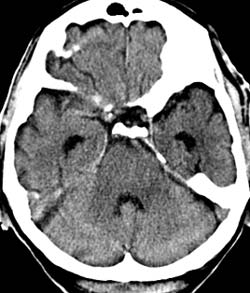

Рис. 7. Влияние коллимации и толщины среза на качество изображений на примере исследования головного мозга. Во всех случаях коллимация 1 мм. (Слева) Реконструированная толщина среза 1 мм. (В центре) Толщина среза 4 мм. (Справа) Толщина среза 8 мм. На изображении (Слева) на область варолиевого моста накладываются артефакты от пирамиды левой височной кости. На изображениях (В центре) и (Справа) они практически отсутствуют - эффект усреднения, однако при толщине среза 8 мм (Справа) нечетко визуализируется ликворное пространство над правой гемисферой мозжечка по той же причине. Толщина среза 4 мм в данном случае оптимальна.